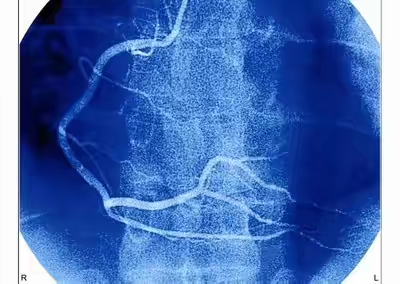

- 冠脉造影:可以理解为升级版的一个放射检查,通过动脉穿刺送入导管到冠脉里面,注射造影剂,可以多角度的观察冠脉的情况,这是冠心病诊断的“金标准”,也就是说如果冠脉造影提示有问题,那就是有问题。如果发现问题还可以同时进行治疗,比如球囊扩张、支架植入等,这种检查是有创的,风险和费用比CT相对高一些,费用大概要三四千块钱,操作风险在冠脉介入治疗成熟的单位是可控的。冠脉造影针对于那一些冠心病怀疑度比较高的患者是比较好的,因为如果这种情况下去做冠脉CT的检查,发现冠脉有问题,那还得再做冠脉造影,才能够明确问题的严重程度。